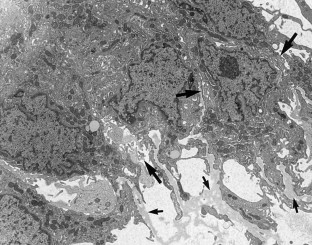

A chordoid glioma in the third ventricle was studied immunohistochemically and ultrastructurally. In this report, special attention is paid to the histogenesis in relation to the pathological appearance and unique anatomic location of this tumor. Light microscopic and immunohistochemical findings were similar to those reported previously. Ultrastructurally, microvilli were frequently seen, but three types of abnormal cilia were rarely observed. Basement membrane around the tumor cells and microvessels was extensive. Poorly to moderately developed intermediate (adherent) junctions were frequently seen. Resemblance of these ultrastructural features of the tumor to embryonic tanycytes suggests the tanycytic differentiation of chordoid glioma. Neuroradiologically, all of the previously reported cases of chordoid gliomas seem to arise in the anterior part of the third ventricular floor. This region includes the lamina terminalis, infundibular recess and median eminence, which corresponds to a tanycyte-rich area. These findings suggest a tanycytic origin of chordoid glioma.

Fig. 4.